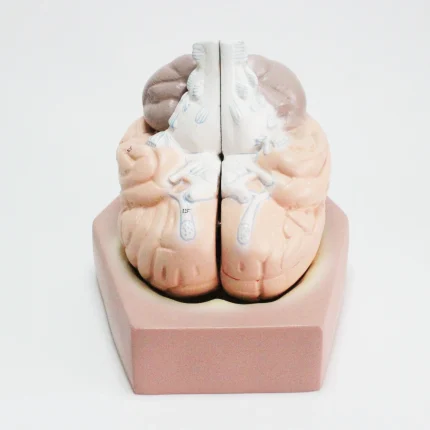

Modèle anatomique de cerveau humain

Modèle de cerveau humain

4 parties : (Fabriqué à partir de fibre de verre)

Modèle anatomique de cerveau humain

4 parties : (Fabriqué à partir de fibre de verre)

Ce cerveau est médialement divisé en deux parties, la moitié droite peut être démontée en frontal avec les lobes parentaux, le tronc cérébral avec les lobes temporaux et occipitaux en deux parties. Placé sur une base amovible avec Key Card numérotée.